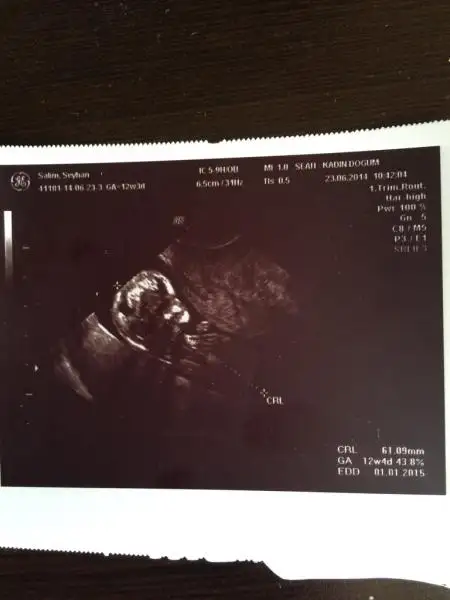

dr soylemeden siz gorun genital nub teorisi ( bebegin cinsiyeti)

4 boyutluda cok belli alin sekli mesela

Benim 4 boyutlu değil ama bakabilirmisiniz nubuna. Şu an 13+0 Daha 10 gün var kontrole. Ilkinde 11 hafta 5 gün,ikincisinde 12 hafta 3 günlüktük.